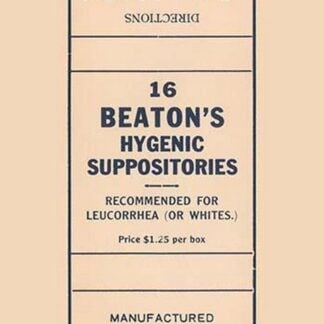

16 Beaton’s Hygenic Suppositories

Price range: $21.99 through $285.99 Select options This product has multiple variants. The options may be chosen on the product page -